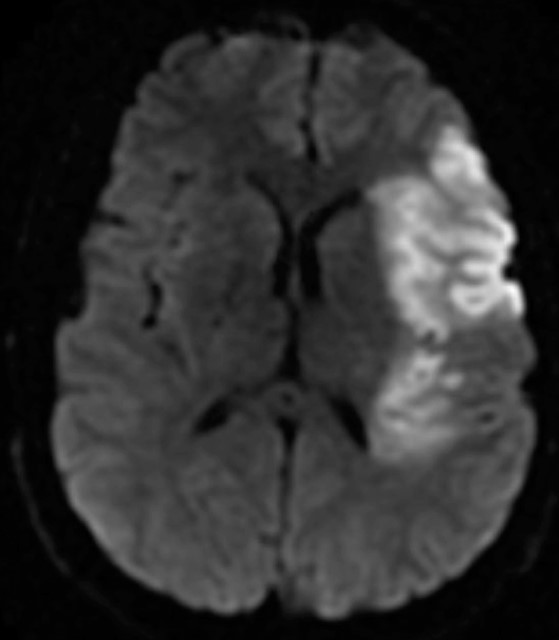

Ci-joint une coupe de l’IRM cérébrale réalisée à 24 heures. La séquence T2* est normale.

Indication théorique à une anticoagulation efficace compte tenu de l’ACFA, mais celle-ci est contre-indiquée dans les premiers jours en raison du risque important de transformation hémorragique (infarctus cérébral constitué, de taille conséquence sur la séquence de diffusion présentée).

Il faut donc prescrire de l’aspirine (diminue le risque de récidive, même si nettement moins efficace que les anticoagulants dans cette indication) et une HBPM préventive (prévention de la phlébite).

Le traitement anticoagulant devra être débuté un peu plus à distance, une fois que le risque de transformation hémorragique aura diminué (pas de consensus, en général 10-15 jours plus tard).